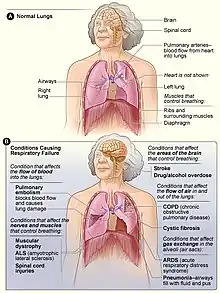

A variety of conditions that can potentially result in respiratory failure.[1] The etiologies of each type of respiratory failure (see below) may differ, as well. Different types of conditions may cause respiratory failure:

- Conditions that reduce the flow of air into and out of the lungs, including physical obstruction by foreign bodies or masses and reduced breathing due to drugs or changes to the chest.[1]

- Conditions that impair the lungs' blood supply. These include thromboembolic conditions and conditions that reduce the output of the right heart, such as right heart failure and some myocardial infarctions.

- Conditions that limit the ability of the lung tissue to exchange oxygen and carbon dioxide between the blood and the air within the lungs. Any disease which can damage the lung tissue can fit into this category. The most common causes are (in no particular order) infections, interstitial lung disease, and pulmonary edema.